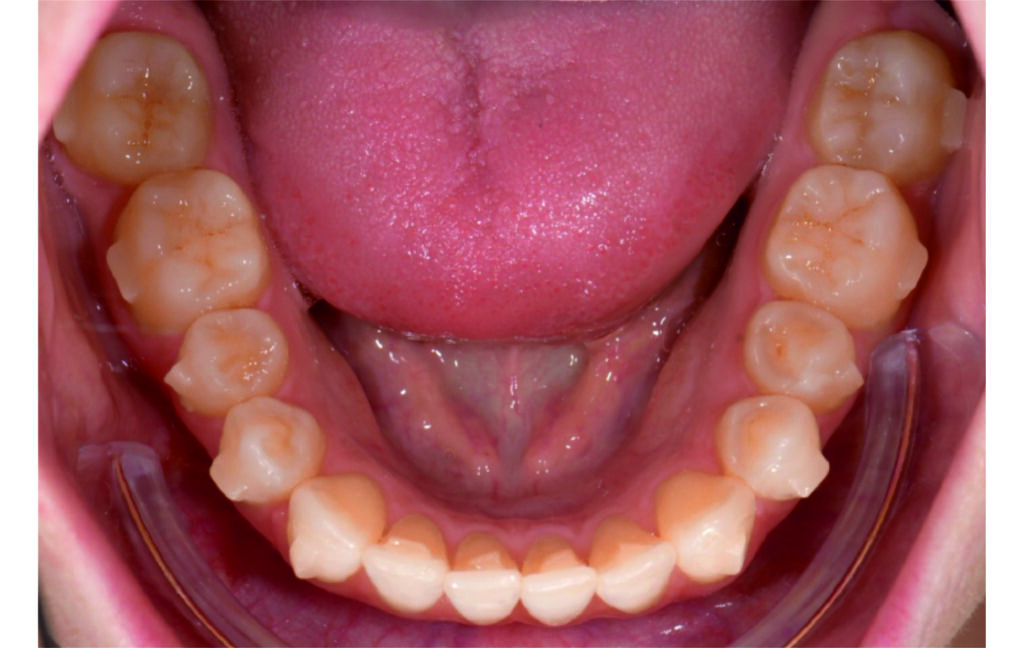

Initial Photos and datas

Clinical examination and diagnosis

Angle Class II 2mm on the right, Angle Class II 2mm on the left, light mandibular asymmetry to the right, lower central line 1mm to the right, upper central line 1,5mm to the left, 1mm overjet and overbite. Sagittal asymmetry of upper dental arch. Light crowding upper and lower frontal segments, severe attrition of posterior teeth, night bruxism. Normal sagittal position of both jaws, high angle case, steep mandibular ramus,excessive lower facial height, open bite tendency.

The case initially presented as a moderate Class II on the right and a Class II tendency on the left, with tapered dental arches and an anterior open bite extending to tooth 26 in segment II.

In segment I, the open bite reached up to the first premolar.

A 1.5 mm deviation of the upper dental midline to the patient’s left was noted, along with a slight mandibular midline shift to the right, likely due to asymmetrical mandibular growth observed in the facial structure. Severe mesial rotations of teeth 16 and 26 were evident in the initial records. As derotation of 16, 26, 17, and 27 progressed up to aligner 16, the premolars in segments I and II moved distally, resulting in a bilateral Class I relationship, as intended in the initial treatment plan.